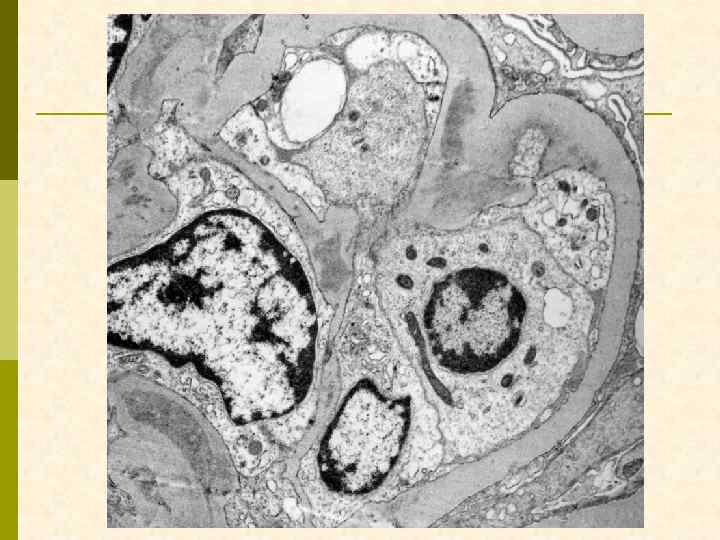

Б. Клинический случай № 21631 Александр К. , 1972 г. рожд. В 1999 г. выявлен гепатит С, в 2003 г. – ВИЧ. С июня 2006 г. – отеки, быстрое развитие анасарки. Почки по УЗИ 13 7 см. Протеинурия 9, 6 г/сут, креатинин 0, 19 мм/л, холестерин 18 мм/л. Обнаружен Ig. M-криоглобулин. 02. 11. 2006 - диагностическая нефробиопсия.

Иммунофлюоресцентное исследование: p Клубочки: Ig. G (2+), Ig. M (3+), C 3 (2+), kappa (3+), lambda (1 -2+) - диффузная, субэндотелиальная и интракапиллярная, крупно-гранулярная экспрессия; p Стенки артериол: C 3 (2+); p Цилиндры: Ig. G (2+), Ig. A (3+), Ig. M (2+), C 3 (3+), kappa (3+), lambda (2+); p Реабсорбированные белковые капли: kappa (3+).

Предварительное гистологическое заключение: p Мембрано-пролиферативный, HCV-ассоциированный, криоглобулинемический(? ) гломерулонефрит с полным склерозом 47% клубочков, сегментарным склерозом 22% клубочков и формированием полулуний в 15% клубочков; p диффузно-очаговый выраженный острый канальцевый некроз; p выраженный артерио-артериолосклероз. Примечание: Криоглобулинемическая природа поражения будет уточняться при ЭМ-исследовании.

Заключение p Мембрано-пролиферативный гломерулонефрит, криоглобулинемический, ВИЧ-ассоциированный, на фоне гепатита С